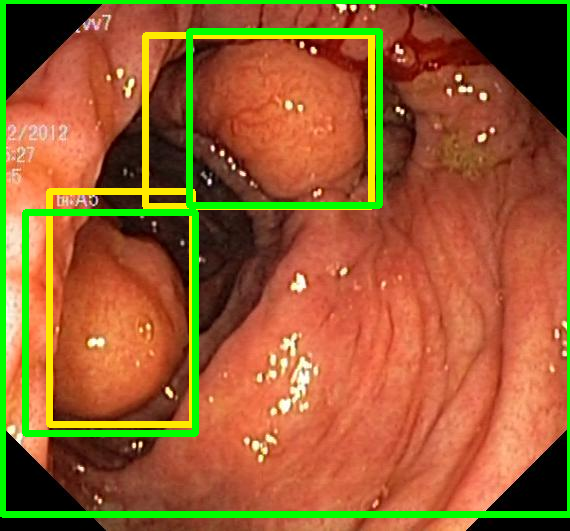

We evaluate the resulting object detection models using the test data, which is pre-processed in the same manner as the validation data, with AP@[.5:.95] (AP for conciseness), AP@.5 (AP50), and AP@.75 (AP75) computed for predicted bounded boxes with a confidence score \geq0.05. For all metrics, a higher value indicates better performance. The results are presented in Table VI, and some examples for predicted bounding boxes with a confidence score \geq0.5 are shown in Fig. 1.

Figure 1: Targets (yellow bounding boxes) and predictions (green bounding boxes) for two randomly selected instances of the Kvasir-SEG test set. For conciseness, we denote ResNet50s with RN, ViT-Bs with VT, Hyperkvasir-unlabelled with HK, ImageNet-1k with IN, MoCo v3 with MC, Barlow Twins with BT, MAE with MA, supervised pretraining with SL, and no pretraining with NA-NA.